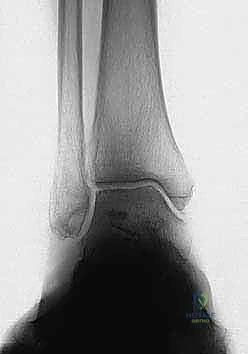

2. التصوير بالأشعة السينية بوضعية الوقوف (Weight-bearing X-rays)

هذا هو حجر الأساس في التشخيص. الأشعة العادية والمريض مستلقٍ لا تظهر الحجم الحقيقي للتشوه. يطلب الدكتور هطيف صوراً خاصة والمريض يحمل وزنه كاملاً على قدميه.

* المنظر الأمامي الخلفي (AP View): لتقييم المسافة المفصلية وتحديد زاوية سطح الساق (Tibial Anterior Surface Angle - TAS).

* منظر سالتزمان (Saltzman View): وهو منظر إشعاعي متخصص جداً لتقييم محاذاة الكعب الخلفي بالنسبة لمحور الساق، وهو أمر حاسم في التخطيط الجراحي.